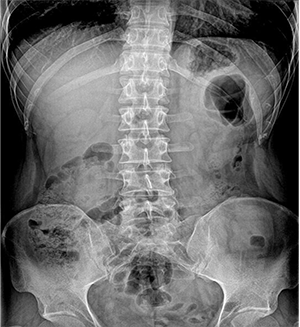

PLD6500系列是普利德研發(fā)的醫(yī)用數(shù)字X線攝影機,采用雙立柱結構,可供各級醫(yī)院放射科對頭部、胸部、腹部、腰椎、四肢等部位進行立位、臥位、正位、側位的數(shù)字攝影檢查。

● 床體運動維度多

無需患者移動即可完成對全身各部位的檢查。